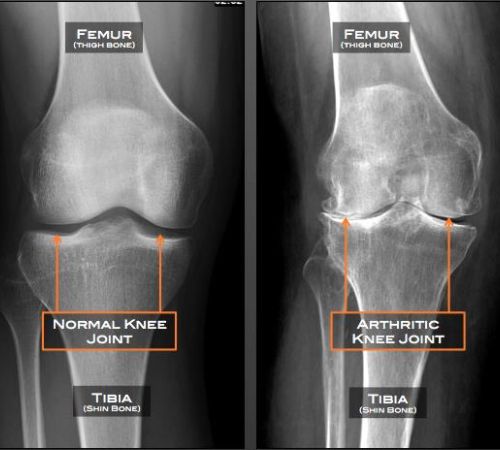

Αποτελεί μια εκφυλιστικού τύπου αρθρίτιδα της άρθρωσης του γόνατος. Με την πάροδο του χρόνου προκαλείται παραμόρφωση της αρθρικής επιφάνειας του γόνατος.

Εμφανίζεται συχνότερα σε γυναίκες προχωρημένης ηλικίας ενώ υπάρχει και γενετικό υπόβαθρο προδιάθεσης. Παρουσιάζει αυξημένη συχνότητα εμφάνισης σε ασθενείς με αυξημένο σωματικό βάρος, ιστορικό μυϊκής ατροφίας, σε άτομα με μεταβολικό σύνδρομο καθώς και σε επαγγελματίες όπου στην καθημερινότητα τους έχουν αυξημένη συχνότητα άρσης βάρους.

Η κλινική εικόνα συνίσταται σε χωλότητα βάδισης με σύνοδο άλγος, σύγκαμψη της άρθρωσης καθώς και απώλεια του φυσιολογικού εύρους κίνησης. Το γόνατο παρουσιάζει διαταραχή του φυσιολογικού άξονα κίνησής του.

Η επιβεβαίωση της διάγνωσης γίνεται με απλή ακτινογραφία.

Η θεραπεία στα αρχικά στάδια αφορά τη χρήση φαρμακευτικής αγωγής, σύσταση για απώλεια βάρους και ενδυνάμωση μυϊκών ομάδων (τετρακεφάλου) καθώς και φυσικοθεραπείες - κινησιοθεραπείες.

Σε γόνατο μη ανταποκρινόμενο στη συντηρητική αγωγή η θεραπεία περιλαμβάνει την χειρουργική αντιμετώπιση με πλήθος σύγχρονων θεραπευτικών τεχνικών - μέσων όπως η μονοδιαμερισματική αρθροπλαστική γόνατος, η ελάχιστα επεμβατική ολική αρθροπλαστική γόνατος καθώς και οι οστεοτομίες κνήμης για νεότερους ασθενείς.

Το χειρουργείο προσφέρει άμεση ανακούφιση από τα συμπτώματα και γρήγορη επάνοδο στην καθημερινότητα.